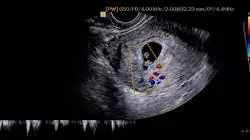

通过大量的科学研究,我们已经在主要的胎盘疾病方面取得了相当的进展。虽然还有很多病因不明确的情况,比如多羊水综合症,但随着科技和技术的不断进步,我们成功提高了胎儿的存活率。这是一段充满发现和突破的旅程 。

这也许是助产士每天要面对的众多工作之一。在高风险情况下,程序和管理的不断进步,提高更加完善的处理胎盘功能不全或脐带异常的方法。在此基础上,TECH 为助产士开设了助产士的胎盘和胎儿附属物病理学及其主要产科急症的最新进展大学课程。

具有丰富临床和教学经验的优秀助产士组成了师资队伍,制定这个密集的高级课程。因此,通过由真正的专家编写的教学大纲,学生将了解到最新的科学证据,以便在发生脐带脱垂、胎盘植入异常或肩难产后的产后护理时采取合理的行动。毕业生可以通过视频摘要、In Focus 视频、专业读物和临床病例模拟,从理论和实践的角度了解不同的胎盘病理以及医护人员在这些情况下所扮演的角色。